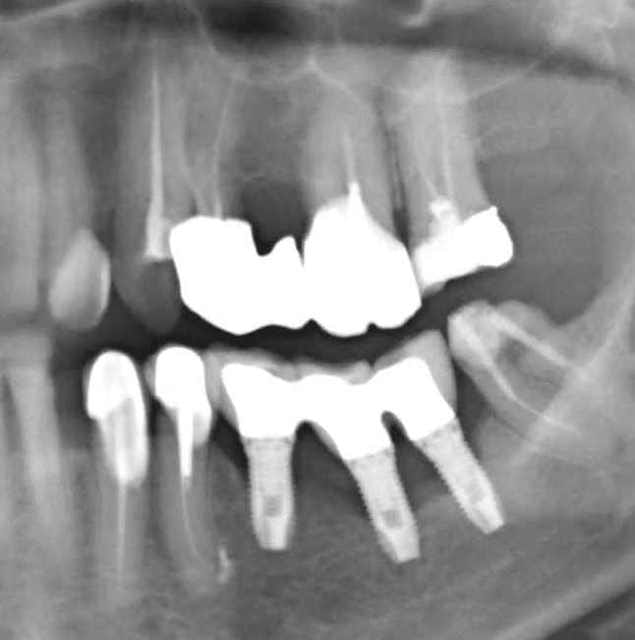

Grossière erreur lors des sutures et exposition de l'os et des implants, malgré tout on continue car belle gencive kératinisée après cicatrisation de ce bordel et résultat au bout de 2 ans ... (entre temps 38 a été virée)